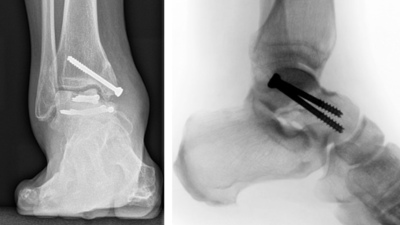

Рентгенографія залишається первинним методом візуалізації. Стандартні проекції включають передньозадню, бічну та mortise-проекцію гомілковостопного суглоба, а також передньозадню, бічну та косу проекції стопи. Додаткова проекція Canale (стопа в положенні підошвового згинання 15°, пронації 15° з направленням променя під кутом 75° до горизонталі) оптимізує візуалізацію шийки таранної кістки.

Методи фіксації: Сучасні методики включають остеосинтез гвинтами (канюльованими або кортикальними), пластинами або їх комбінацією. Анатомічна репозиція суглобових поверхонь є критичною для профілактики посттравматичного артрозу. Фіксація має забезпечувати достатню стабільність при мінімальному порушенні васкуляризації.